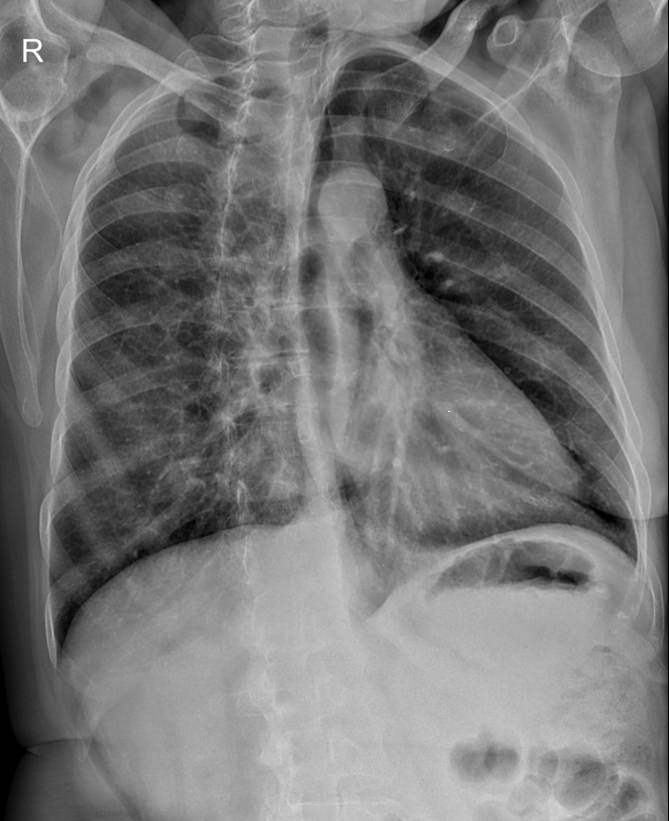

В качестве основного метода исследования при патологии ребер назначают рентгенодиагностику. Это простой и доступный способ узнать состояние костной ткани изнутри, не нарушая целостности кожных покровов. минимальная доза излучения современных рентгеновских аппаратов делает рентгенографию безопасной.

Что покажет рентген ребер (прицельно)

На рентгенограмме будут видны:

• Перелом и его локализация;

• Отек, отломки и осколки кости и инородные тела в мягких тканях;

• При рентгене верхних ребер ― возможные повреждения тканей легких, трахеи, пищевода;

• При обследовании нижних ребер ― повреждение тканей и органов верхней части живота: печени, селезенки, почек, диафрагмы.